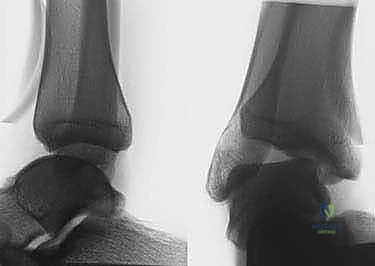

التشخيص الدقيق: منهجية الأستاذ الدكتور محمد هطيف

- التقييم السريري الدقيق: يتضمن اختبار الدرج الأمامي (Anterior Drawer Test) لتقييم رباط ATFL، واختبار إمالة الكاحل (Talar Tilt Test) لتقييم رباط CFL.

- الأشعة السينية (X-rays) مع اختبار الإجهاد: صور أشعة عادية لاستبعاد الكسور أو النتوءات العظمية، وصور أثناء الضغط على المفصل لقياس زاوية عدم الاستقرار بدقة.

- الرنين المغناطيسي (MRI): وهو الفحص الأهم لتقييم جودة الأربطة المتبقية، والكشف عن أي إصابات مصاحبة في الغضاريف (Osteochondral Lesions) أو تمزقات في الأوتار الشظوية.